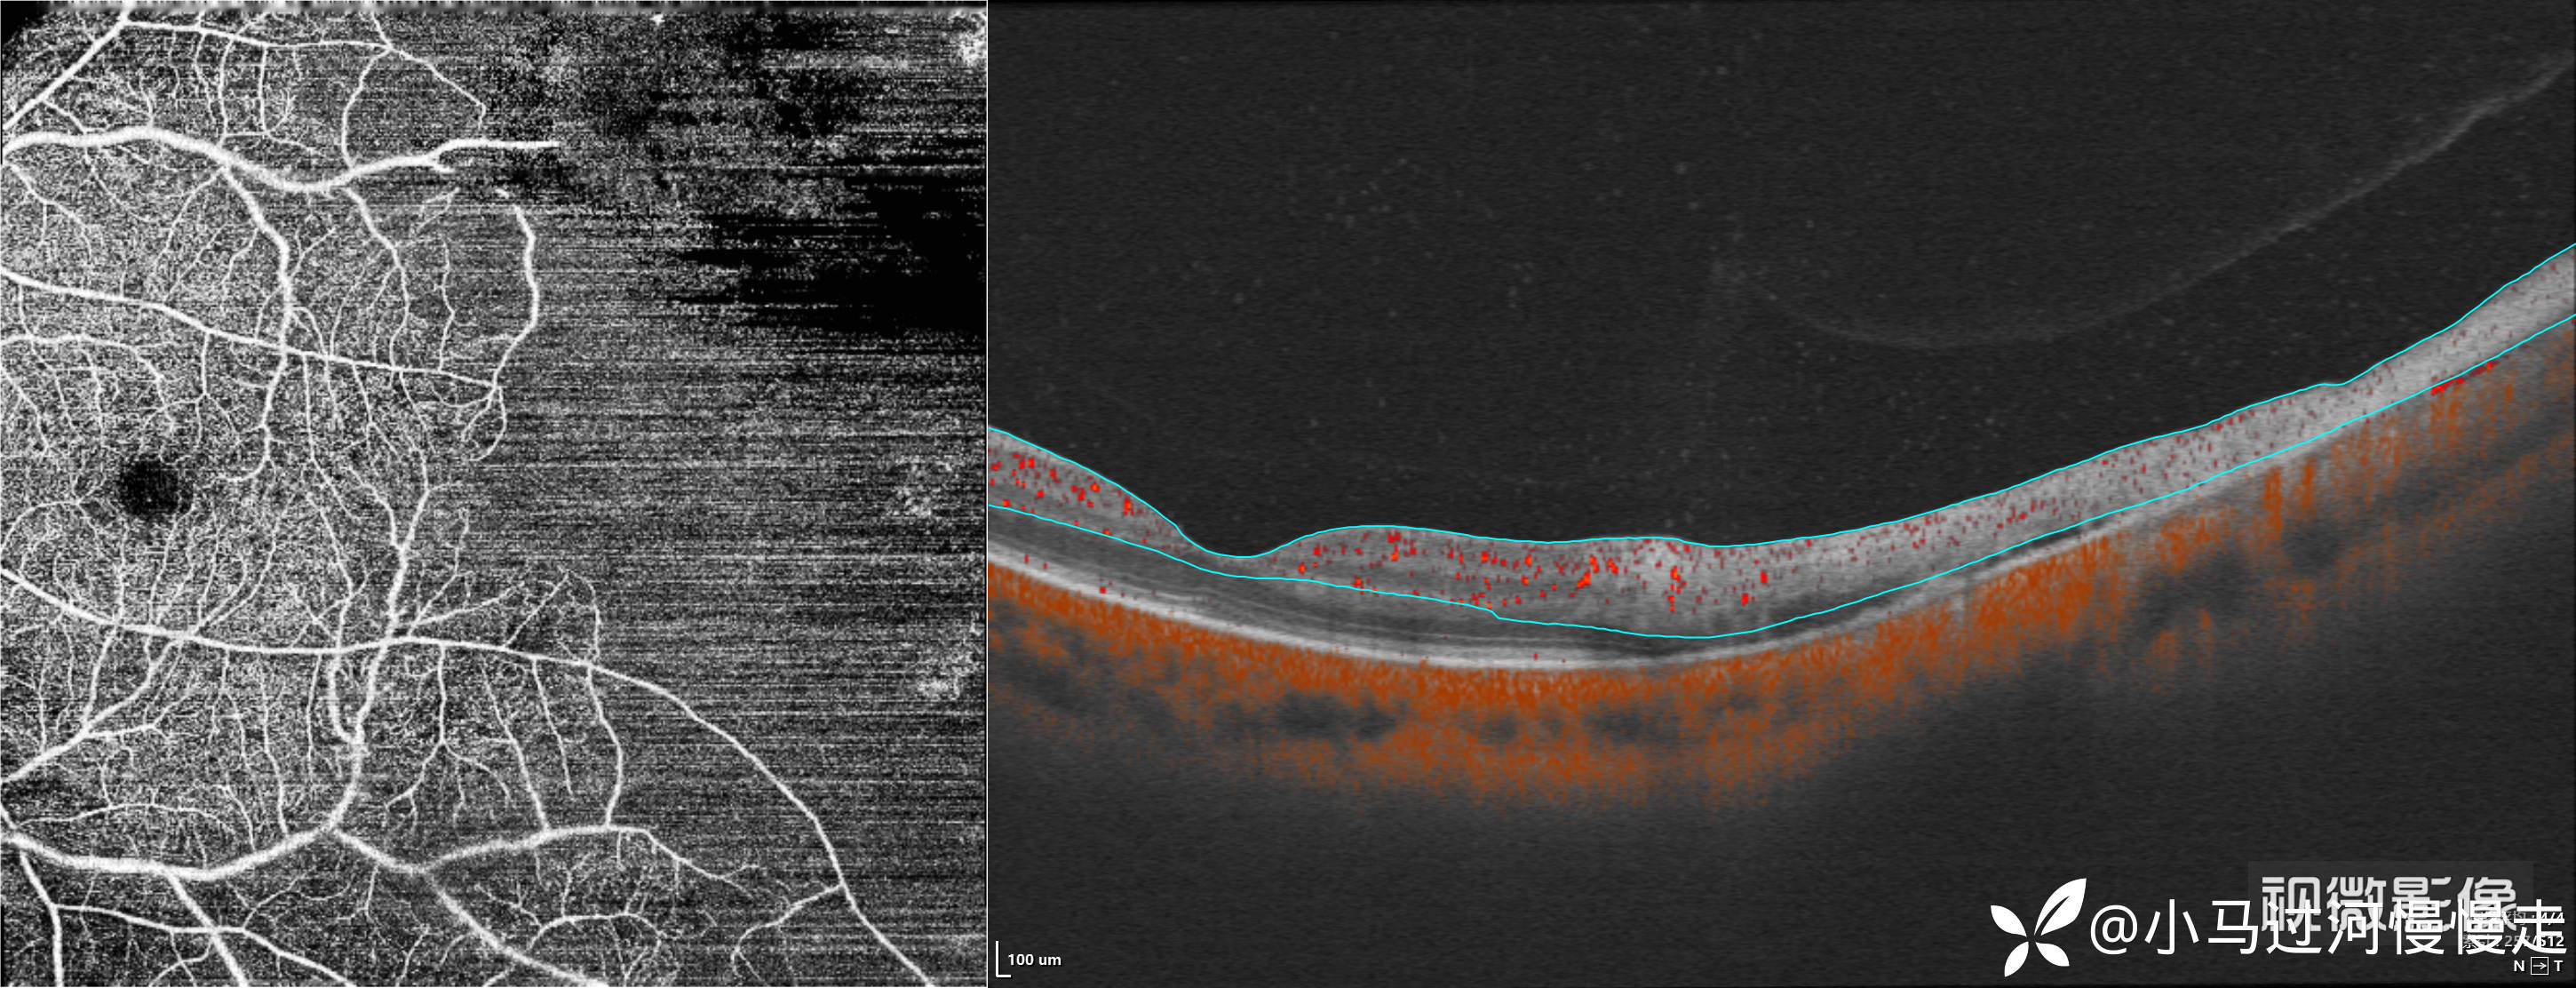

患者是HIV感染者,就诊时外院已经确诊了AIDS。右眼底正常,左眼底表现为霜枝样静脉炎及颞侧"番茄炒蛋"样病变,病变中心可见坏死灶:

当时正在试用视微SSOCT,记录了左眼颞侧病变的影像。

依据患者AIDS病史,典型的眼部表现初步诊断了巨细胞病毒性视网膜炎(CMVR),后患者外院就诊确诊了CMVR,没有回来复查,这是我唯一见过的HIV合并CMVR的病例。